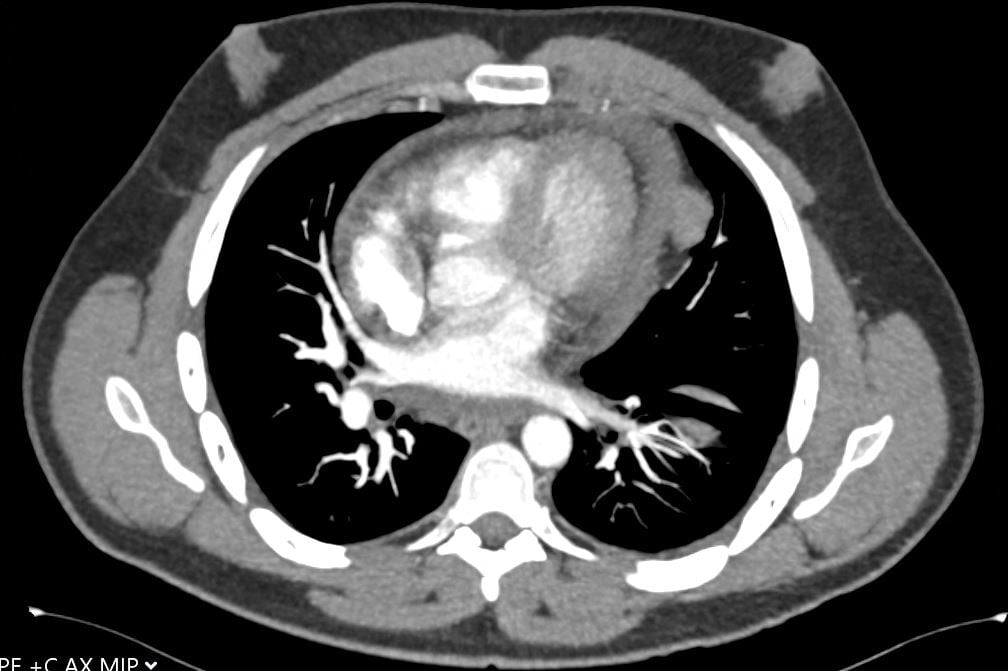

A 30-year-old man presents with dyspnea and is found to have an anterior mediastinal mass, as well as supraclavicular lymphadenopathy; biopsy of the mass is consistent with thymic carcinoma. Imaging shows his anterior mediastinal mass, lung and diaphragmatic lesions consistent with metastatic malignancy, and probable pericardial involvement with small pericardial effusion (Figures 1, 2, 3, and 4).

Fig. 3: CT image showing large mediastinal mass found to be thymic carcinoma. -

Fig. 4: CT image showing small pericardial effusion. -